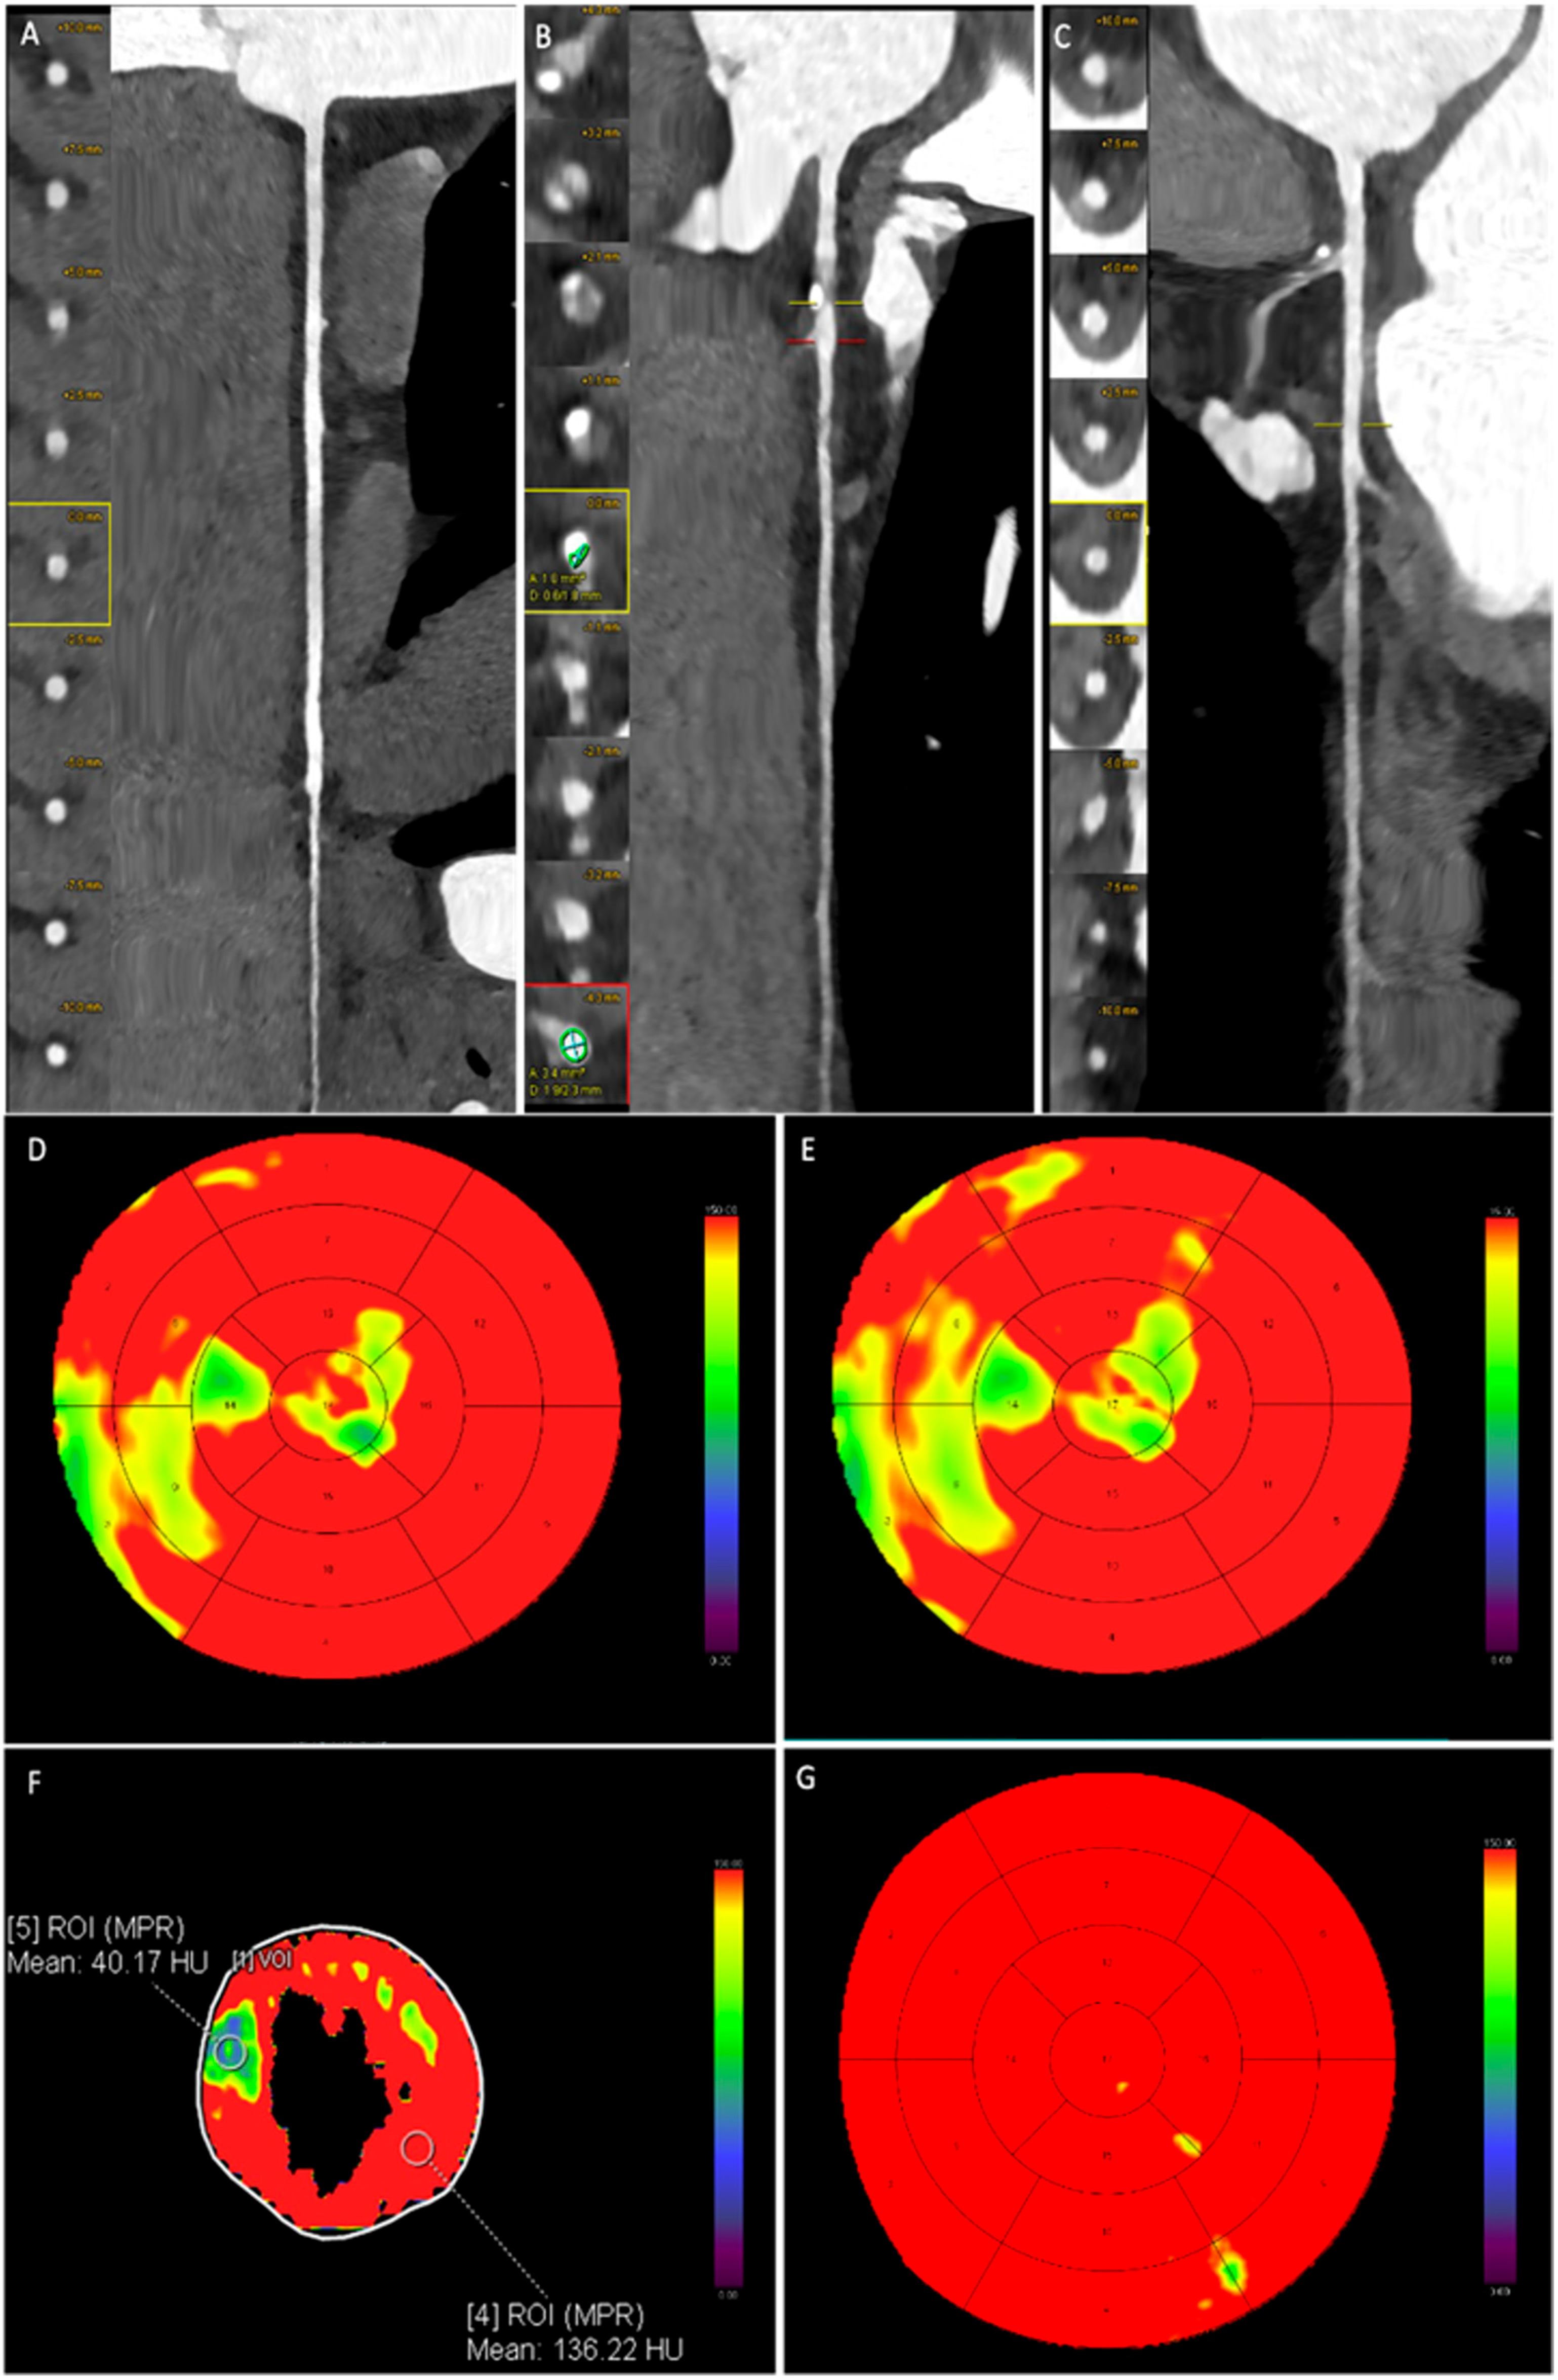

Figure 3 and Figure 4 present representative cases from our study. Figure 2 depicts a patient with moderate coronary artery stenosis without evidence of myocardial hypoperfusion, whereas Figure 3 illustrates a patient with moderate stenosis associated with stress-induced myocardial hypoperfusion.

Figure 4.

Male patient, 61 years old, with atypical chest pain. Coronary CT angiography reveals a regularly perfused right coronary artery without significant stenosis (A). The left anterior descending artery shows a single moderate stenosis with diameter reduction between 50 and 69%, located on a high-risk plaque at the proximal segment (B). The circumflex artery is regularly perfused and free from significant stenosis (C). Dynamic stress CT myocardial perfusion imaging highlights reduced myocardial perfusion in some basal, mid, and apical septal segments ((D,E), yellow-green area). In the subsequent post-processing (F), the reduction in blood flow is quantitatively assessed by placing a region of interest (ROI) in hypoperfused segments and compared with reference segments. (G) shows the normal myocardial vascularization during the baseline evaluation of CCTA.